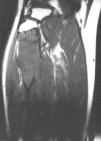

Fig. 5.--Secuencia coronal T1-ES. La lesión aparece homogéneamente hipointensa, de comportamiento expansivo, limitada superiormente por la phisis.

La RM permite una clara delimitación entre el hueso normal y el tumoral. Generalmente aparece hipointenso tanto en las secuencias T1 como T2, como los linfomas o los tumores fibrosos, debido a la densa matriz conectiva, y para algunos autores debido a la relativa hipocelularidad, lo que significa una disminución de los protones móviles6. Otros autores recogen otros hallazgos, como la presencia de una pseudocápsula, focos de necrosis, niveles líquido-líquido dentro del tumor8 y, en ocasiones, un comportamiento hiperintenso en las secuencias T22,4. En nuestro caso se identificaban dos componentes diferentes dentro de la misma lesión de diferente señal en las secuencias T2. El componente superior es hipointenso y el inferior de intensidad intermedia. En las secuencias dinámicas postgadolinio intravenoso, el componente superior mostraba un leve realce periférico en fase tardía con prácticamente nulo realce en fase precoz y el componente inferior presentaba intenso realce en fase precoz, que persistía en fases tardías.